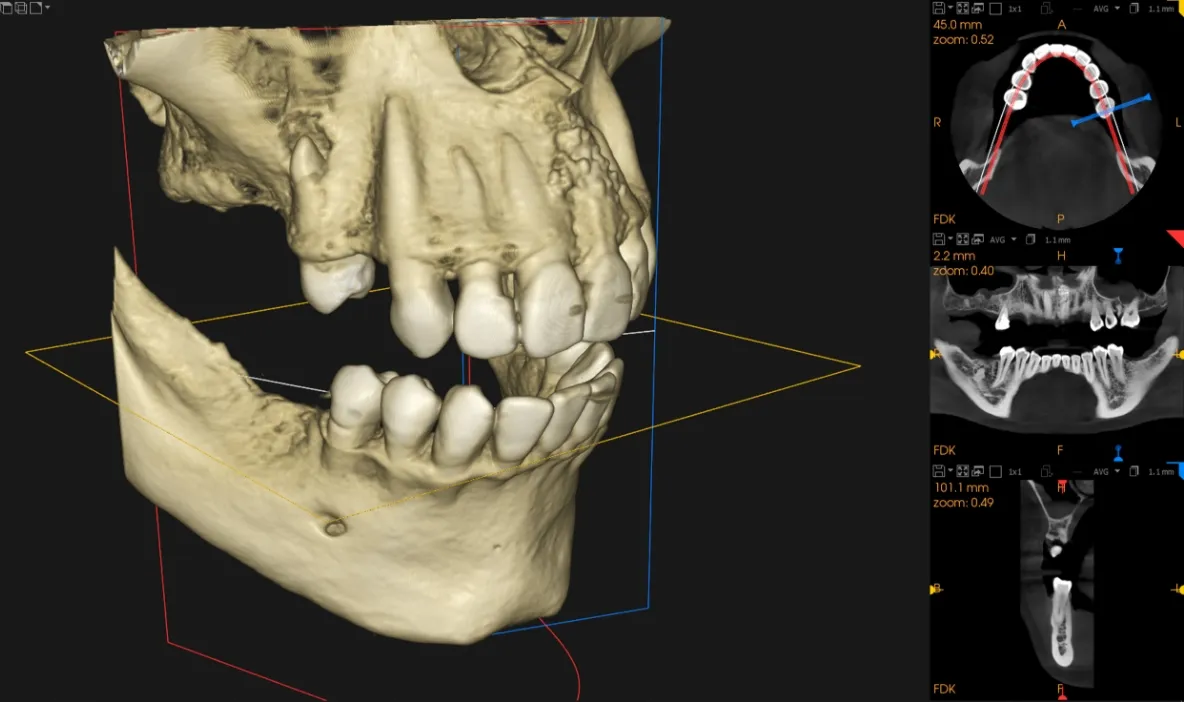

デジタル技術を活用し、

痛みを抑えた精度の高い

インプラント治療

- 他院で断られたケースでも「難症例」に対応

- 1回で終わる手術「抜歯即時埋入」

- 「骨の少ない方」でも対応

- 安心の「10年保証」

失った歯を補う方法の1つで、インプラントが歯根の代わりを果たすことで天然歯に近い噛み心地を再現します。当院ではサージカルガイドを使用することで、より精密な埋入を可能とし、術後の痛みや腫れを軽減しています。機能性だけでなく審美性も回復します。